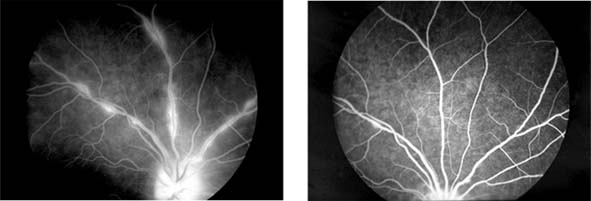

Retinal Branch Vein Occlusion (new window  Figure 15-8)

Occlusion of a branch vein should be viewed as part of the spectrum of central retinal vein occlusion. Investigations are similar in the two conditions, but arterial disease-particularly hypertension-is common. Branch retinal vein occlusion occurs more frequently in the superotemporal and inferotemporal regions and particularly at sites where arteries cross over veins, and only rarely where veins cross over arteries.

Figure 15-8

Figure 15-8: Retinal branch vein occlusion. The affected segment of retina shows changes of reduced perfusion. This results in irregularity of the arterioles and veins, areas of capillary closure, and dilated capillaries with microaneurysms.

The value of laser treatment in the management of the complications of branch retinal vein occlusion is discussed in Chapters 10 and 24.